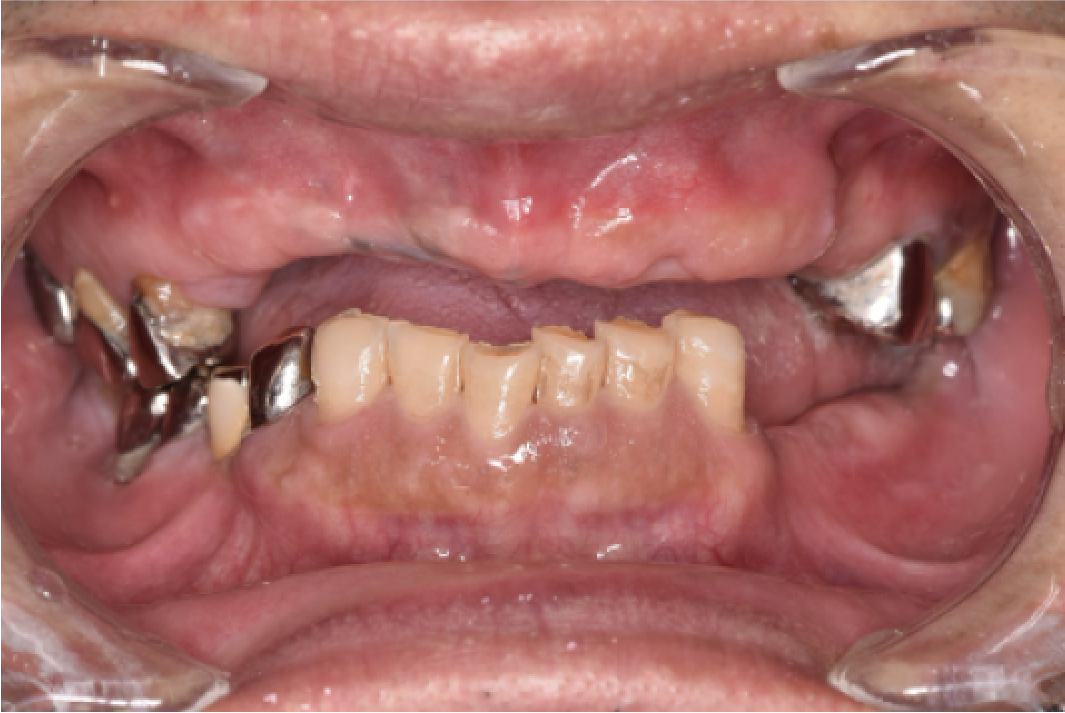

CASE01

■ 治療内容

上下顎All-on-4インプラント治療

■ 治療費用

7,438,000円(税込)

■ 治療期間

約10ヶ月

■ リスク

治療後の腫れや出血、またメンテナンスを怠ることで周囲炎のリスクあります。